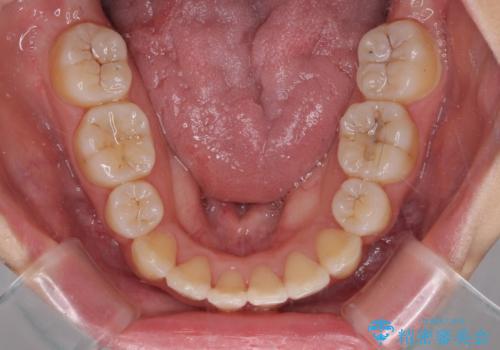

移動量が多かったため、治療期間は通常より半年~1年ほど長くかかりましたが、上下の正中をほぼ同じ位置にまで移動させることができました。